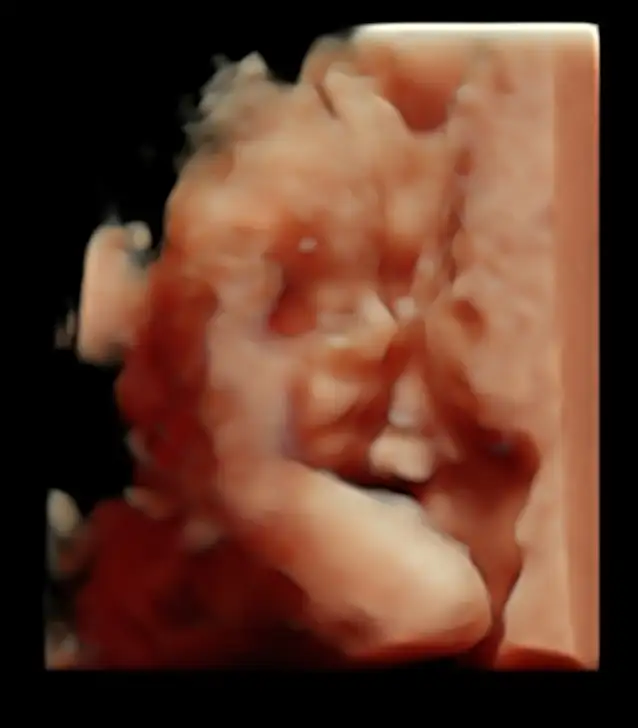

Buda ilk 4 boyutlu fotoğrafımız 😍😍